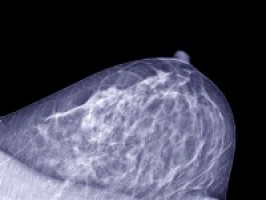

Researchers have identified a new regulatory pathway that may play an important role in basal-like breast cancer (BLBC), a particularly aggressive form of breast cancer often referred to as "triple negative."

While targeted cancer drugs are an option for some types of breast cancer, BLBCs are generally unresponsive.

Additionally, these tumours tend to metastasise rapidly and patients with this disease generally have a worse clinical prognosis. The aggressive nature of this subtype of breast cancer may be due to the fact that these tumours often harbour a higher content of cancer stem cells (CSCs).